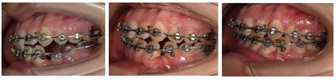

矫治过程:初戴时上下颌全口牙列黏结Tip-Edge Plus托槽及磨牙颊面管,上下颌牙列放置0.014镍钛丝。上颌弓丝更换的顺序为:0.016镍钛丝,0.018镍钛丝,0.016×0.022镍钛丝,0.018×0.025镍钛丝,0.018×0.025不锈钢方丝。下颌弓丝更换顺序为:0.016镍钛丝,0.018镍钛丝,0.020不锈钢圆丝,0.016×0.022镍钛丝,0.018×0.025镍钛丝,0.018×0.025不锈钢方丝。下颌弓丝更换至0.020不锈钢圆丝时,口腔外科拔除74牙,34牙开窗,黏结牵引装置。牵引装置与下颌弓丝之间弹性牵引。同时为防止埋伏牙两侧的牙齿因受牵引力向中间倾斜,在33牙位的托槽上安装牙根向远中倾斜的正轴簧,35牙位的托槽上安装牙根向近中倾斜的正轴簧。待34牙冠完全萌出后,34牙去除牵引装置,黏结托槽,在主弓丝为0.020不锈钢圆丝不变的前提下,于下颌托槽的辅弓管内放置0.012 NiTi丝辅助排齐,待34牙冠牵引到正常高度后,34牙位的托槽安装牙根向近中的正轴簧用来竖直牙根。最后阶段精细调整,对齐上下颌中线,关闭剩余间隙(图2)。

矫治结果及保持:矫治结束后,患者牙齿排列整齐,双侧尖牙磨牙中性关系,前牙覆盖正常,上下牙列中线居中。X线显示,牙根基本正常,无明显吸收(图3,表1)。保持一年后复查,矫治效果稳定,无复发。34牙无松动,根尖片显示,34牙根正常,牙根周围牙周膜间隙正常。牙周科检查:34牙龈色粉红,无探诊出血,无牙周深袋(图4)。

本病例采用CBCT三维图像,对阻生牙的位置提供矢状面、冠状面及轴面等多平面的重建图像,且精度高,不存在失真的随意放大及旋转。通过CBCT对阻生前磨牙准确定位,确定外科手术开窗的部位和正畸牵引力的方向。本病例中,34的萌出间隙是足够的,不用额外扩展间隙。矫治前CBCT显示34牙根发育正常,仅根尖处1 mm左右的牙根弯曲,34牙周膜影像清晰,与周围骨质无粘连,与35牙根无粘连。采用Tip-Edge Plus技术,利用硬度较高的不锈钢丝作为承受牵引力的钢丝,同时托槽的竖管安装正轴簧,控制牙轴,以免加重缺牙间隙两侧的牙齿向缺隙侧倾斜,为埋伏牙的牵引提供了足够的支抗需求。该牙的牵引过程主要包括两个阶段,第一阶段是通过垂直向的牵引力,先把埋伏牙牵引出牙龈外,待牙冠高度接近合平面,同时牙冠颊侧面暴露充分以后,进入第二阶段,即在牙齿的颊侧黏结托槽,利用该托槽自带的竖管安装正轴簧,辅助竖直牙轴。另外该患者配合度极高,能坚持按约复诊,且有良好的口腔卫生习惯,这也是埋伏牙牵引成功的条件之一。最终经过系统矫正,成功牵引出埋伏阻生牙,排齐上下牙列,建立良好的咬合关系。